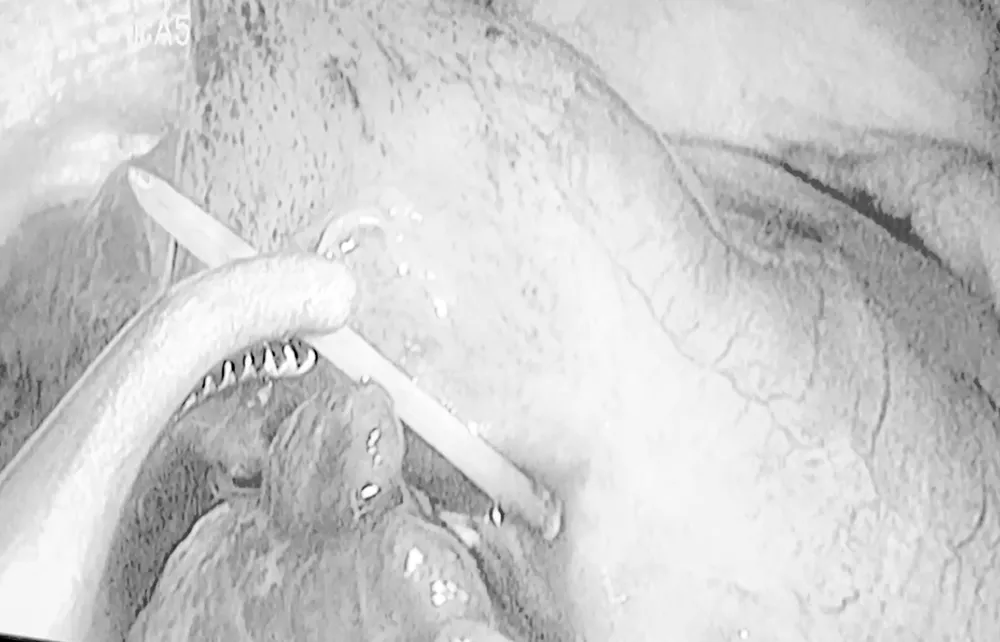

Tại khoa cấp cứu, các bác sĩ thăm khám kỹ lưỡng, chỉ định xét nghiệm, siêu âm, chụp Xquang. Kết quả chẩn đoán đây là trường hợp đau bụng ngoại khoa do dị vật trong ruột, phải mổ khẩn. BSCK2 Phạm Ngọc Tảo, Trưởng khoa Ngoại tổng hợp, Bệnh viện An Bình, cho biết, ê kíp phẫu thuật nội soi đã thám sát và phát hiện dị vật có kích thước 0,2cm x 4cm giống tăm xỉa răng, đâm thủng hồi tràng đoạn cuối ruột non. Bác sĩ tiến hành khâu lỗ thủng ruột, cắt ruột thừa viêm thứ phát, tổng thời gian phẫu thuật 60 phút.

Theo bác sĩ Tảo, nếu không phát hiện sớm và xử lý kịp thời, bệnh nhân sẽ bị viêm phúc mạc toàn thể do xì dịch ruột, ảnh hưởng đến tính mạng. Hậu phẫu ngày 2, bệnh nhân ổn định, bụng mềm, được theo dõi sát và hướng dẫn ăn uống phù hợp. Người bệnh chia sẻ: “Tôi ít khi dùng tăm khi ăn cơm nên không biết đã nuốt phải dị vật khi nào".